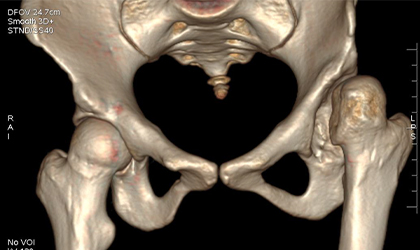

26-year-old woman diagnosed with hip dysplasia characterized by a shallow hip socket. She underwent a left total hip replacement using a specialized prosthesis known as the S-ROM system. Additionally, bone grafting was performed to reconstruct and reinforce the socket walls for better implant support.This is one of the youngest girls I have done a hip replacement in. Did her right hip when she was 13 and the left a year later. She is a blood cancer survivor. She had collapse of both her hips related to chemotherapy (which actually saved her life). She had ceramic bearings. Presently totally symptom free pursuing her higher studies.